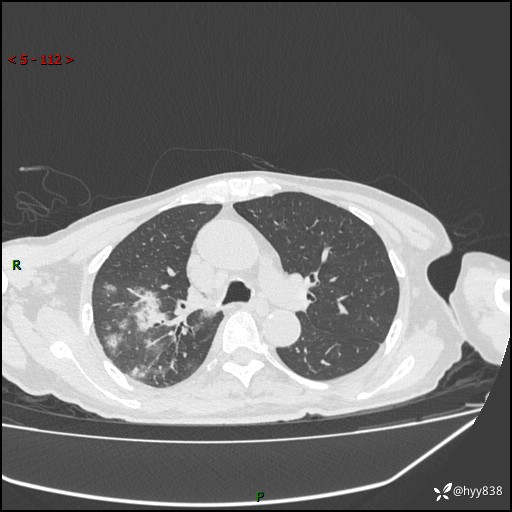

第一次胸部CT检查